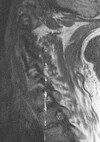

Is this a T1 or T2 weighted image?

T2 weighted image